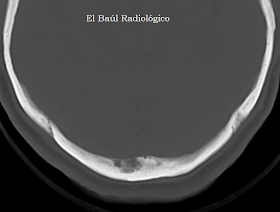

CASO 1)

Varón de 91 años.

FIGURA 1-A) En esta imagen de TC se aprecia una impronta diplóica característica. Comunica con la cavidad craneal y no depende de ninguna vena intracraneal. La localización en el hueso occipital, es muy típica.

FIGURA 1-B) Con ventana de hueso, se aprecia con mayor nitidez. Es polilobulada y de contorno escleroso, lo cual indica crecimiento lento, benigno.